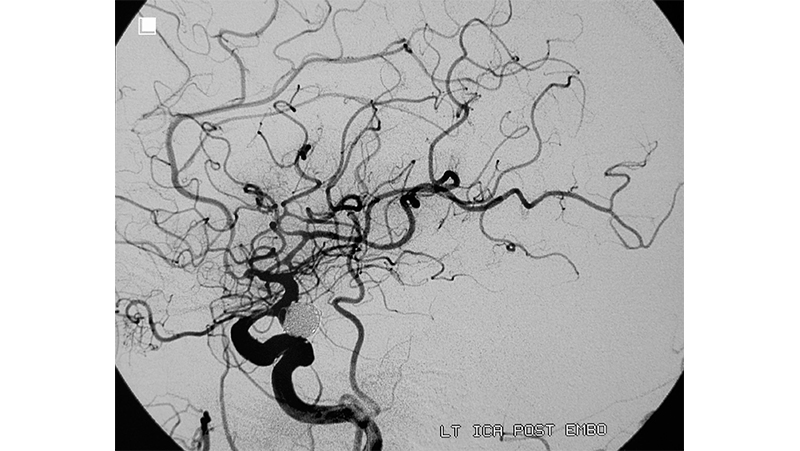

Εικόνα 3: 24 ώρες αργότερα η ασθενής επιβαρύνθηκε κλινικά και διασωληνώθηκε εκ νέου λόγω πτώσεως του επιπέδου συνειδήσεως. Σε νέο αγγειογραφικό έλεγχο βλέπουμε την υποτροπή του αγγειοσπάσμου με ελαττωση της παρεγχυματογραφίας του αριστερού ημισφαιρίου.